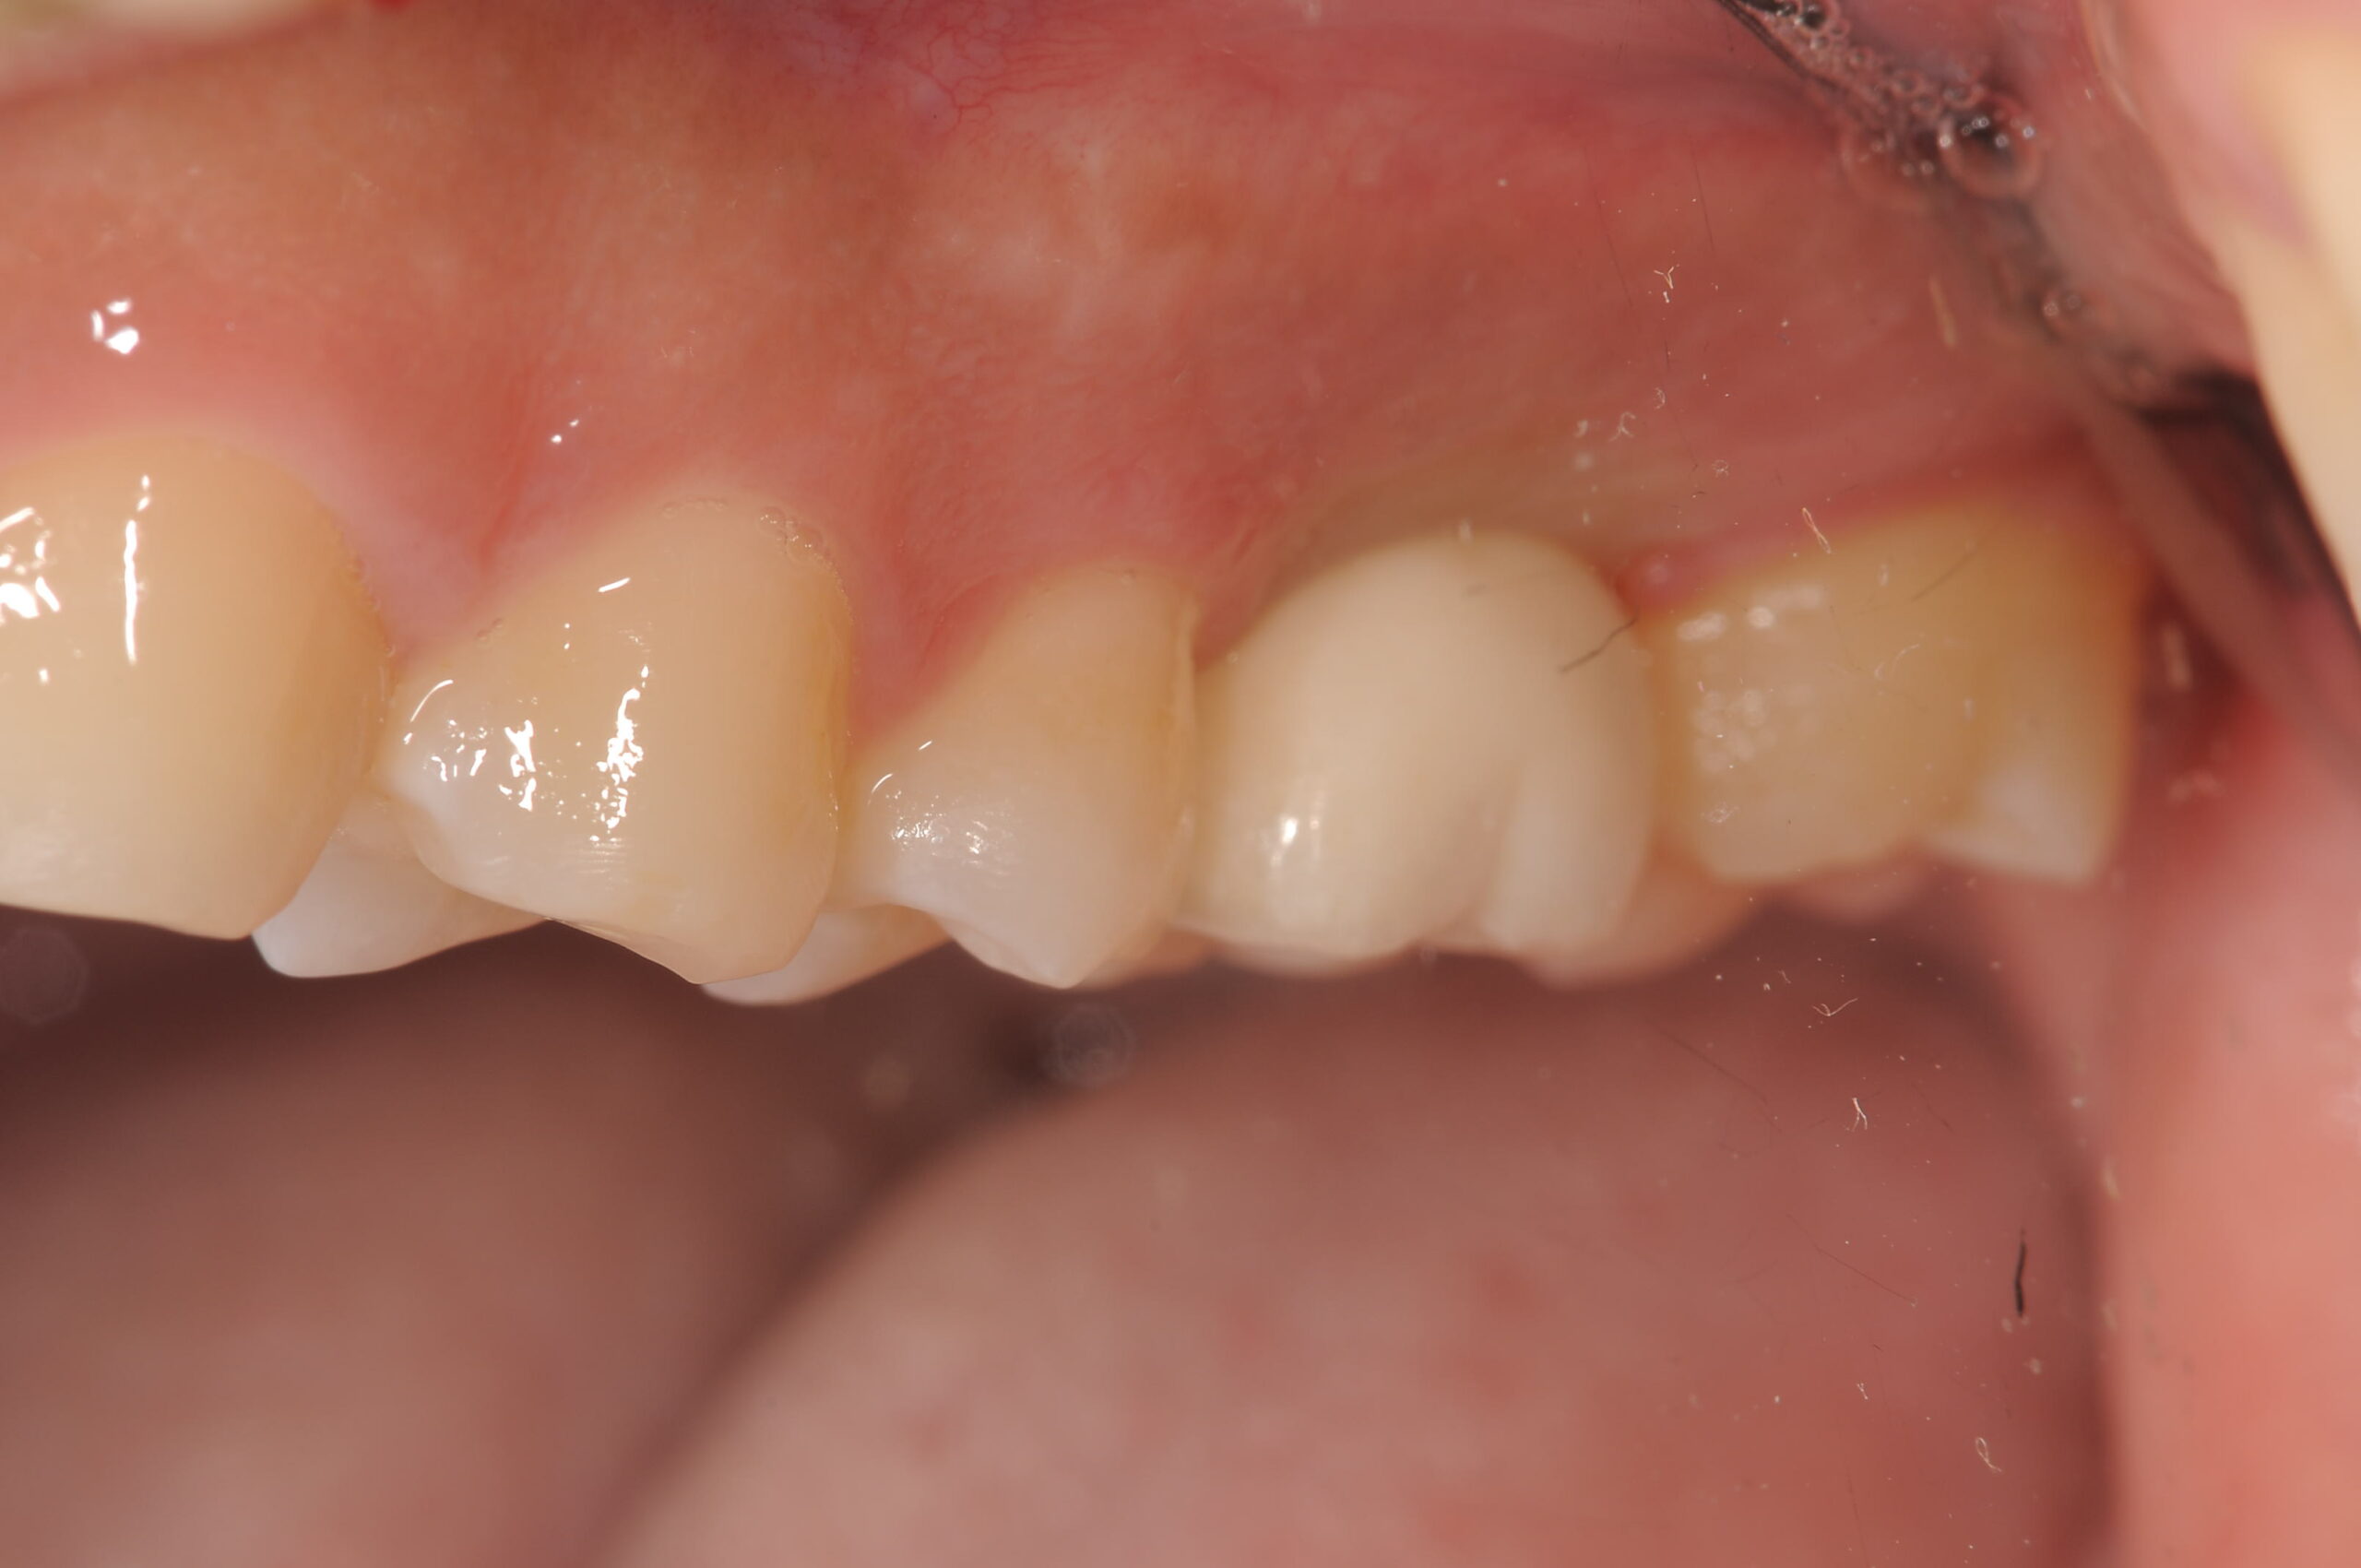

歯が入ったところは、こんな感じです。